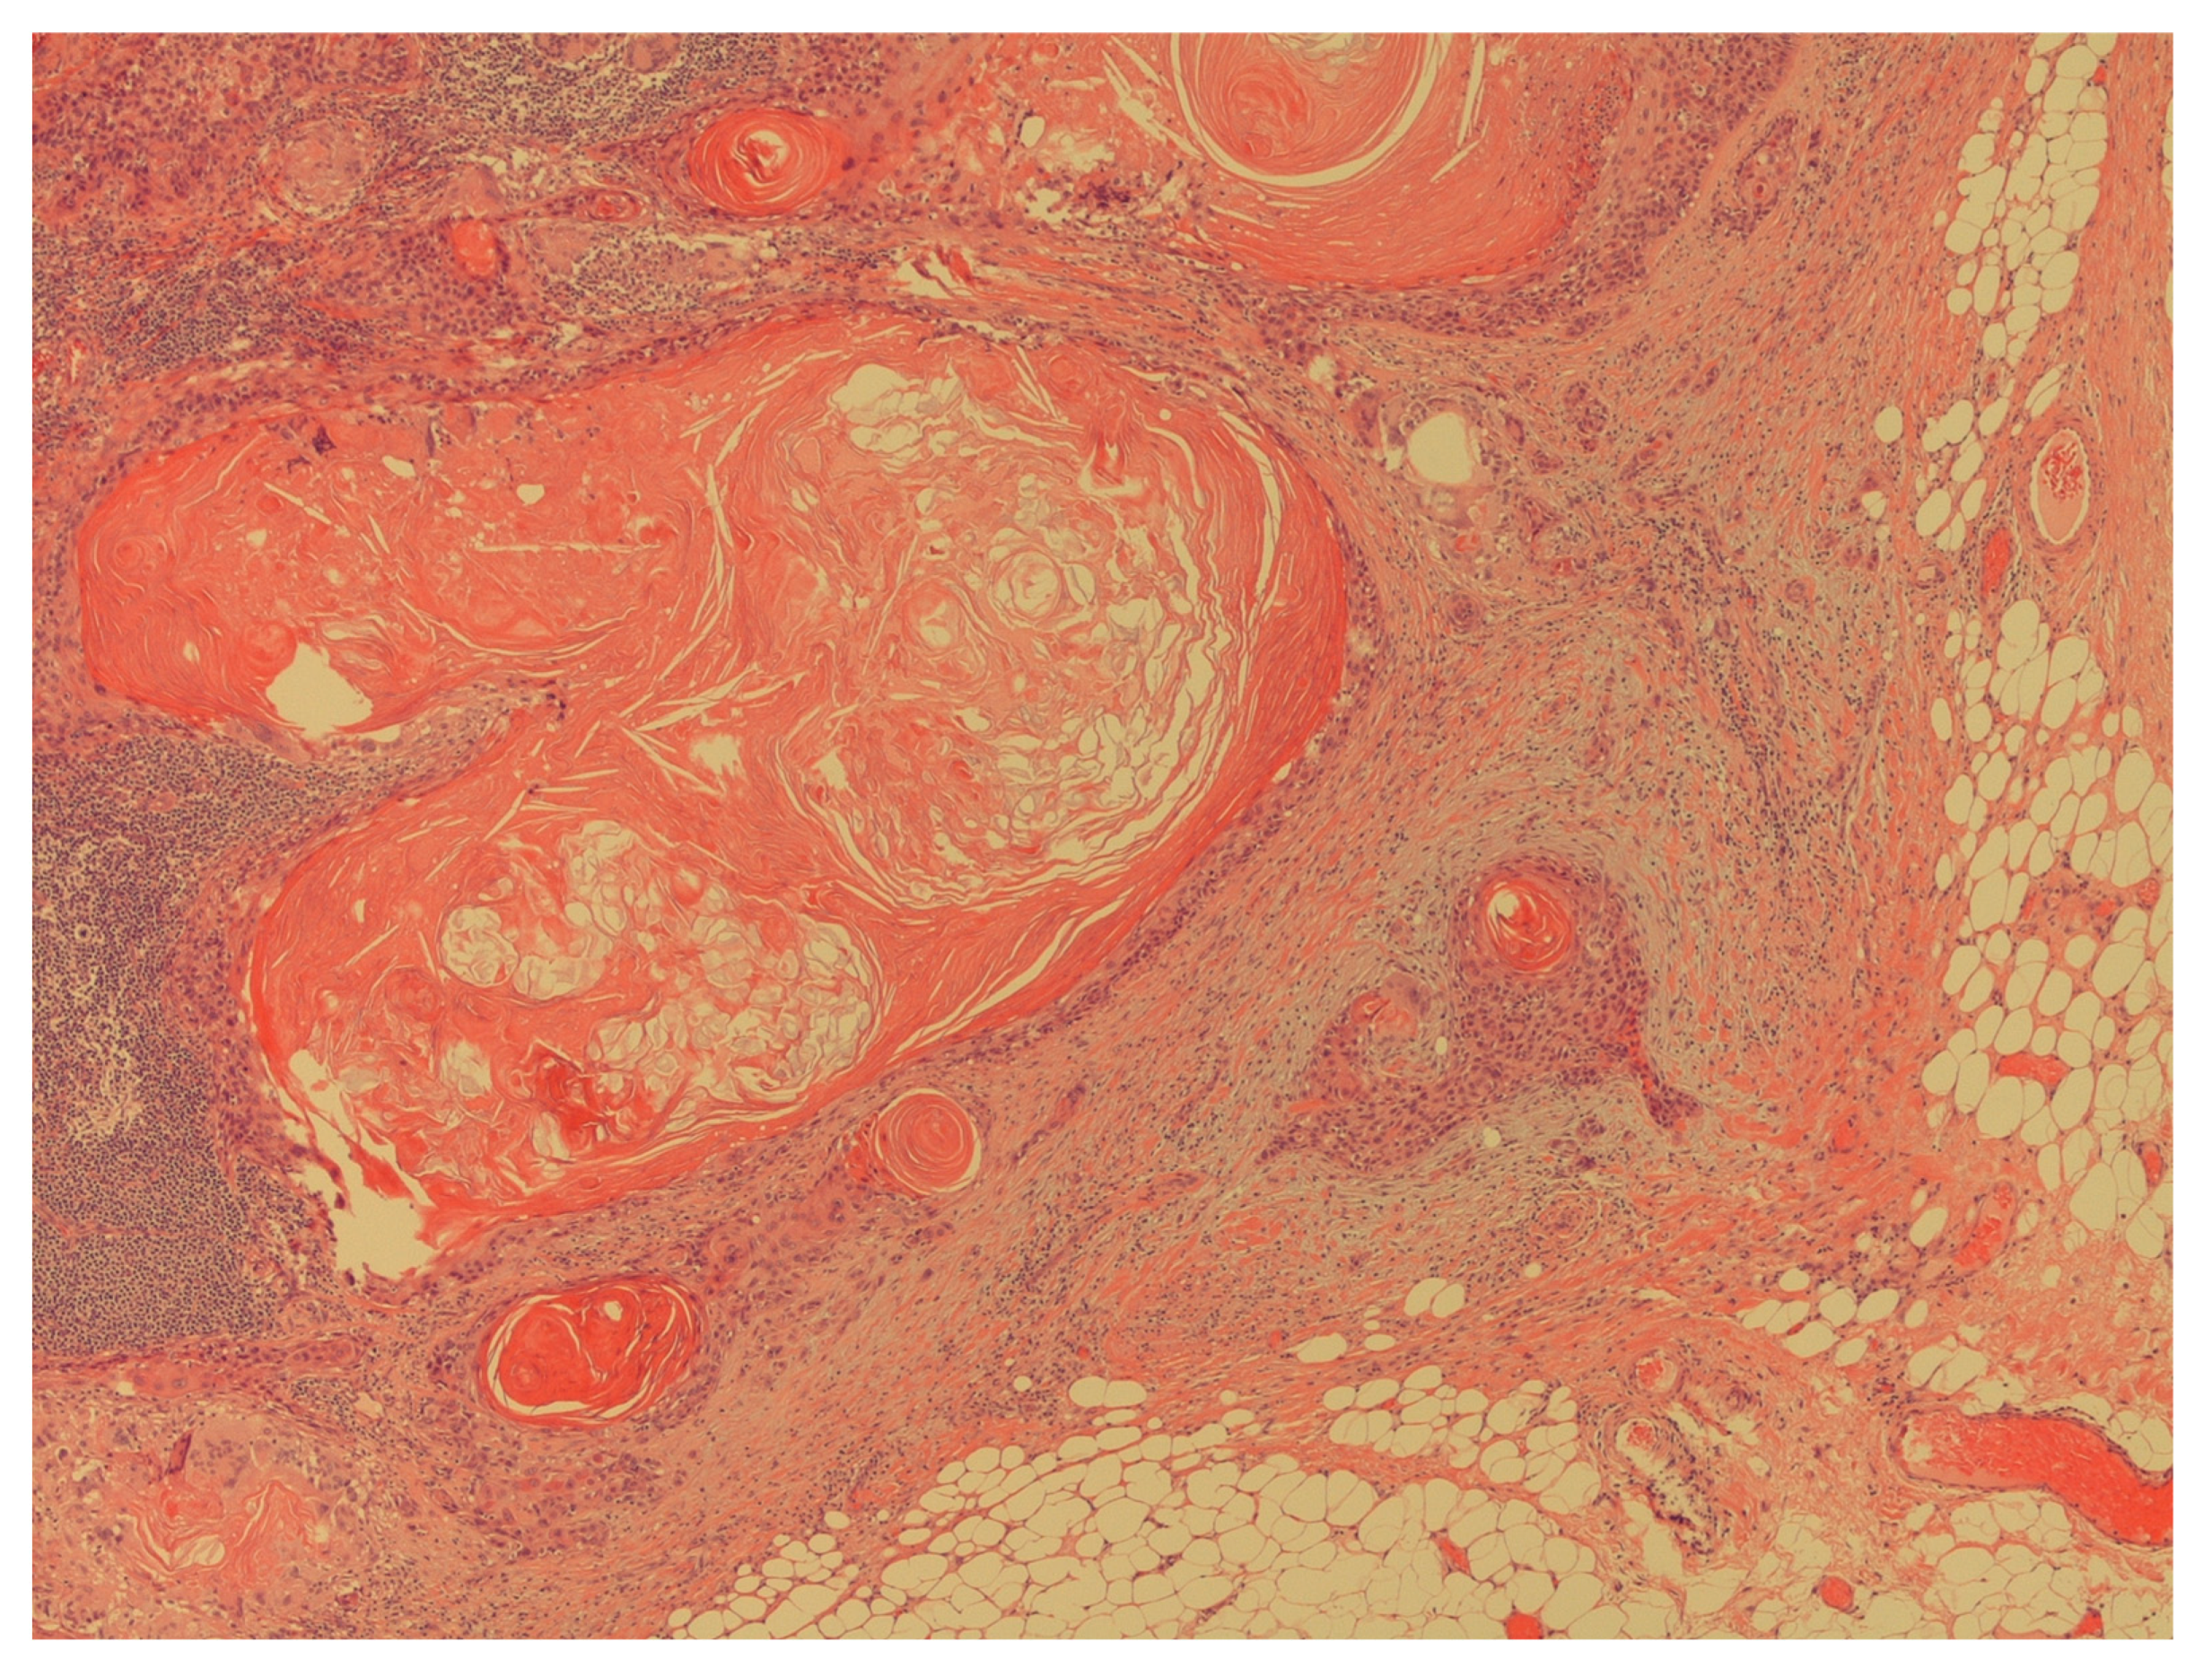

Figure 5. The figure shows an extracapsular neoplastic extension by foci of squamous cell carcinoma (H&E; 40X).